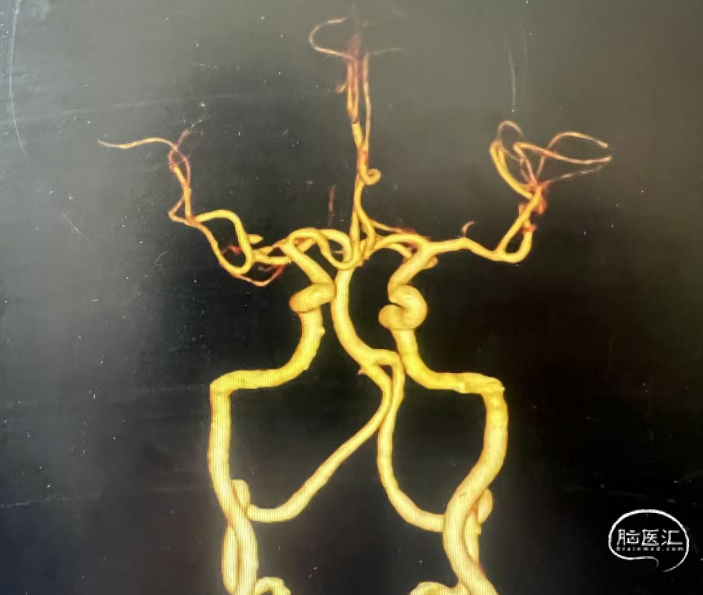

头颈CTA示:右侧大脑中动脉重度狭窄。

高清血管壁MRI示:右侧大脑中动脉M1段重度狭窄;环形强化,内膜增生,斑块形成。

术中证实右侧大脑中动脉M1中段重度狭窄。